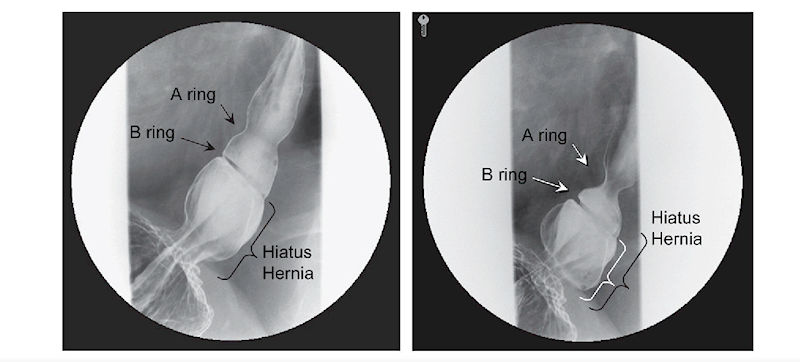

Рентген с контрастом (барием) — рентген грудной клетки использует для получения чёрно-белых изображений внутренней части грудной полости, где расположен пищевод чтобы определить размер и тип ГПОД.

Эзофагограмма — это своего рода видеорентген пищевода в действии. Она снимает видео внутренней части пищевода в режиме реального времени во время глотания.